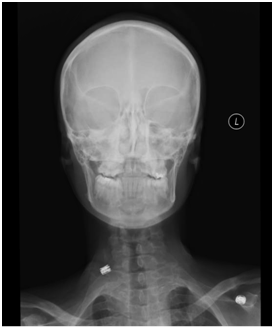

32-year-old African-American lady with history of rickets secondary to severe vitamin D deficiency since 3 years of age presented to emergency room (ER) with fatigue and severe carpo-pedal spasms. The patient had history of rickets and was on replacement with calcium carbonate and vitamin D. She was prescribed 50,000 units of vitamin D monthly by her primary care physician; however she was not adherent to the treatment regimen. Her past history included history of fracture at age 3 and a traumatic fracture of left femur at age 29, which required intramedullary rod placement with subsequent intramedullary rod placement on right side for fracture prevention (Figure1). Based on T score on DEXA scan (T-score not known as report was not available), she was diagnosed with osteoporosis and she received one dose of denosumab (60mg subcutaneous). Within 24 hours of administration of denosumab she developed, numbness and tingling along with spasms in both upper and lower extremities which worsened over the next day when she presented to the ER and was found to be severely hypocalcemic with an ionized calcium of 2.2mg/dL (4.7-5.3) and total calcium of 4.7 mg/dL (8.5-10.5). She had low magnesium of 1.1 mg/dL (1.7-2.7), phosphate of 2.7 mg/dL (2.5-4.8) and low 25 OH Vitamin D of 17 ng/mL (30-100) with elevated intact PTH levels of 428 pg/ml (12-72). Her 1,25 Dihydroxy vitamin D levels were 37.2 pg/mL (10-75).

Figure 1 X Ray Pelvis (Antero-posterior view) with bilateral intramedullary rod placement.